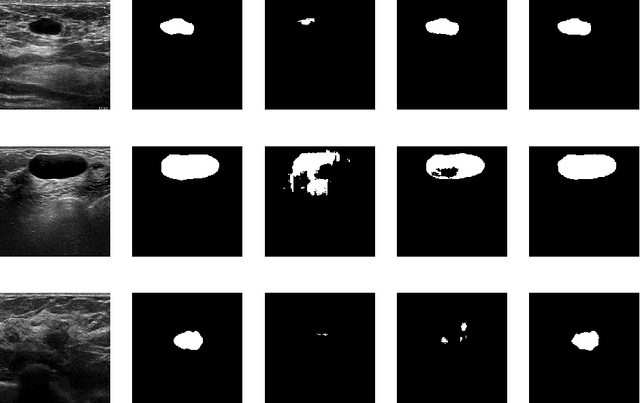

Abstract:Fine-tuning a network which has been trained on a large dataset is an alternative to full training in order to overcome the problem of scarce and expensive data in medical applications. While the shallow layers of the network are usually kept unchanged, deeper layers are modified according to the new dataset. This approach may not work for ultrasound images due to their drastically different appearance. In this study, we investigated the effect of fine-tuning different layers of a U-Net which was trained on segmentation of natural images in breast ultrasound image segmentation. Tuning the contracting part and fixing the expanding part resulted in substantially better results compared to fixing the contracting part and tuning the expanding part. Furthermore, we showed that starting to fine-tune the U-Net from the shallow layers and gradually including more layers will lead to a better performance compared to fine-tuning the network from the deep layers moving back to shallow layers. We did not observe the same results on segmentation of X-ray images, which have different salient features compared to ultrasound, it may therefore be more appropriate to fine-tune the shallow layers rather than deep layers. Shallow layers learn lower level features (including speckle pattern, and probably the noise and artifact properties) which are critical in automatic segmentation in this modality.

Abstract:Ultrasound (US) is one of the most commonly used imaging modalities in both diagnosis and surgical interventions due to its low-cost, safety, and non-invasive characteristic. US image segmentation is currently a unique challenge because of the presence of speckle noise. As manual segmentation requires considerable efforts and time, the development of automatic segmentation algorithms has attracted researchers attention. Although recent methodologies based on convolutional neural networks have shown promising performances, their success relies on the availability of a large number of training data, which is prohibitively difficult for many applications. Therefore, in this study we propose the use of simulated US images and natural images as auxiliary datasets in order to pre-train our segmentation network, and then to fine-tune with limited in vivo data. We show that with as little as 19 in vivo images, fine-tuning the pre-trained network improves the dice score by 21% compared to training from scratch. We also demonstrate that if the same number of natural and simulation US images is available, pre-training on simulation data is preferable.